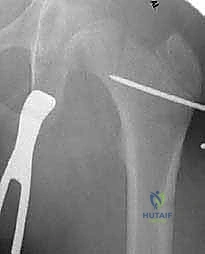

جراحة قطع عظم الفخذ الداني التقويمي (Varus Osteotomy) هي إجراء جراحي هندسي يتم فيه:

1. إجراء قطع دقيق (Osteotomy) في الجزء العلوي من عظم الفخذ.

2. إزالة إسفين عظمي صغير (Wedge) أو ببساطة إعادة توجيه العظمة.

3. إغلاق الفجوة لتقليل الزاوية (مثلاً من 150 درجة إلى 120 درجة).

4. تثبيت العظمة في الوضع الجديد باستخدام شريحة معدنية قوية جداً، وغالباً ما تكون شريحة نصلية بزاوية 90 درجة (90-Degree Blade Plate).

الأهداف الاستراتيجية للجراحة:

- الاحتواء العميق (Containment): جعل رأس الفخذ يغوص بشكل أعمق وأكثر أماناً داخل الحُق.

- تحسين الميكانيكا الحيوية: إعادة توجيه العضلات المحيطة بالورك (خاصة العضلات المبعدة) لتعمل بكفاءة أكبر، مما يقضي على العرج.

- إنقاذ المفصل (Joint Preservation): تأخير أو منع الحاجة إلى زراعة مفصل ورك صناعي في المستقبل.

يتم إدخال نصل الشريحة ذات الزاوية 90 درجة في المسار الذي تم تحضيره في عنق الفخذ. ثم يتم ضم جزئي العظم المقطوعين معاً (إغلاق الفجوة)، مما يؤدي فوراً إلى تغيير زاوية عنق الفخذ إلى الوضع الطبيعي الجديد. يتم تثبيت الجزء الطويل من الشريحة على جسم عظم الفخذ باستخدام براغي قوية من التيتانيوم أو الفولاذ الطبي المقاوم للصدأ.

بعد التأكد من صلابة التثبيت ووضعية المفصل المثالية عبر الأشعة، يتم غسل الجرح وإغلاقه بطبقات متعددة باستخدام خيوط تجميلية لتقليل الندبات.